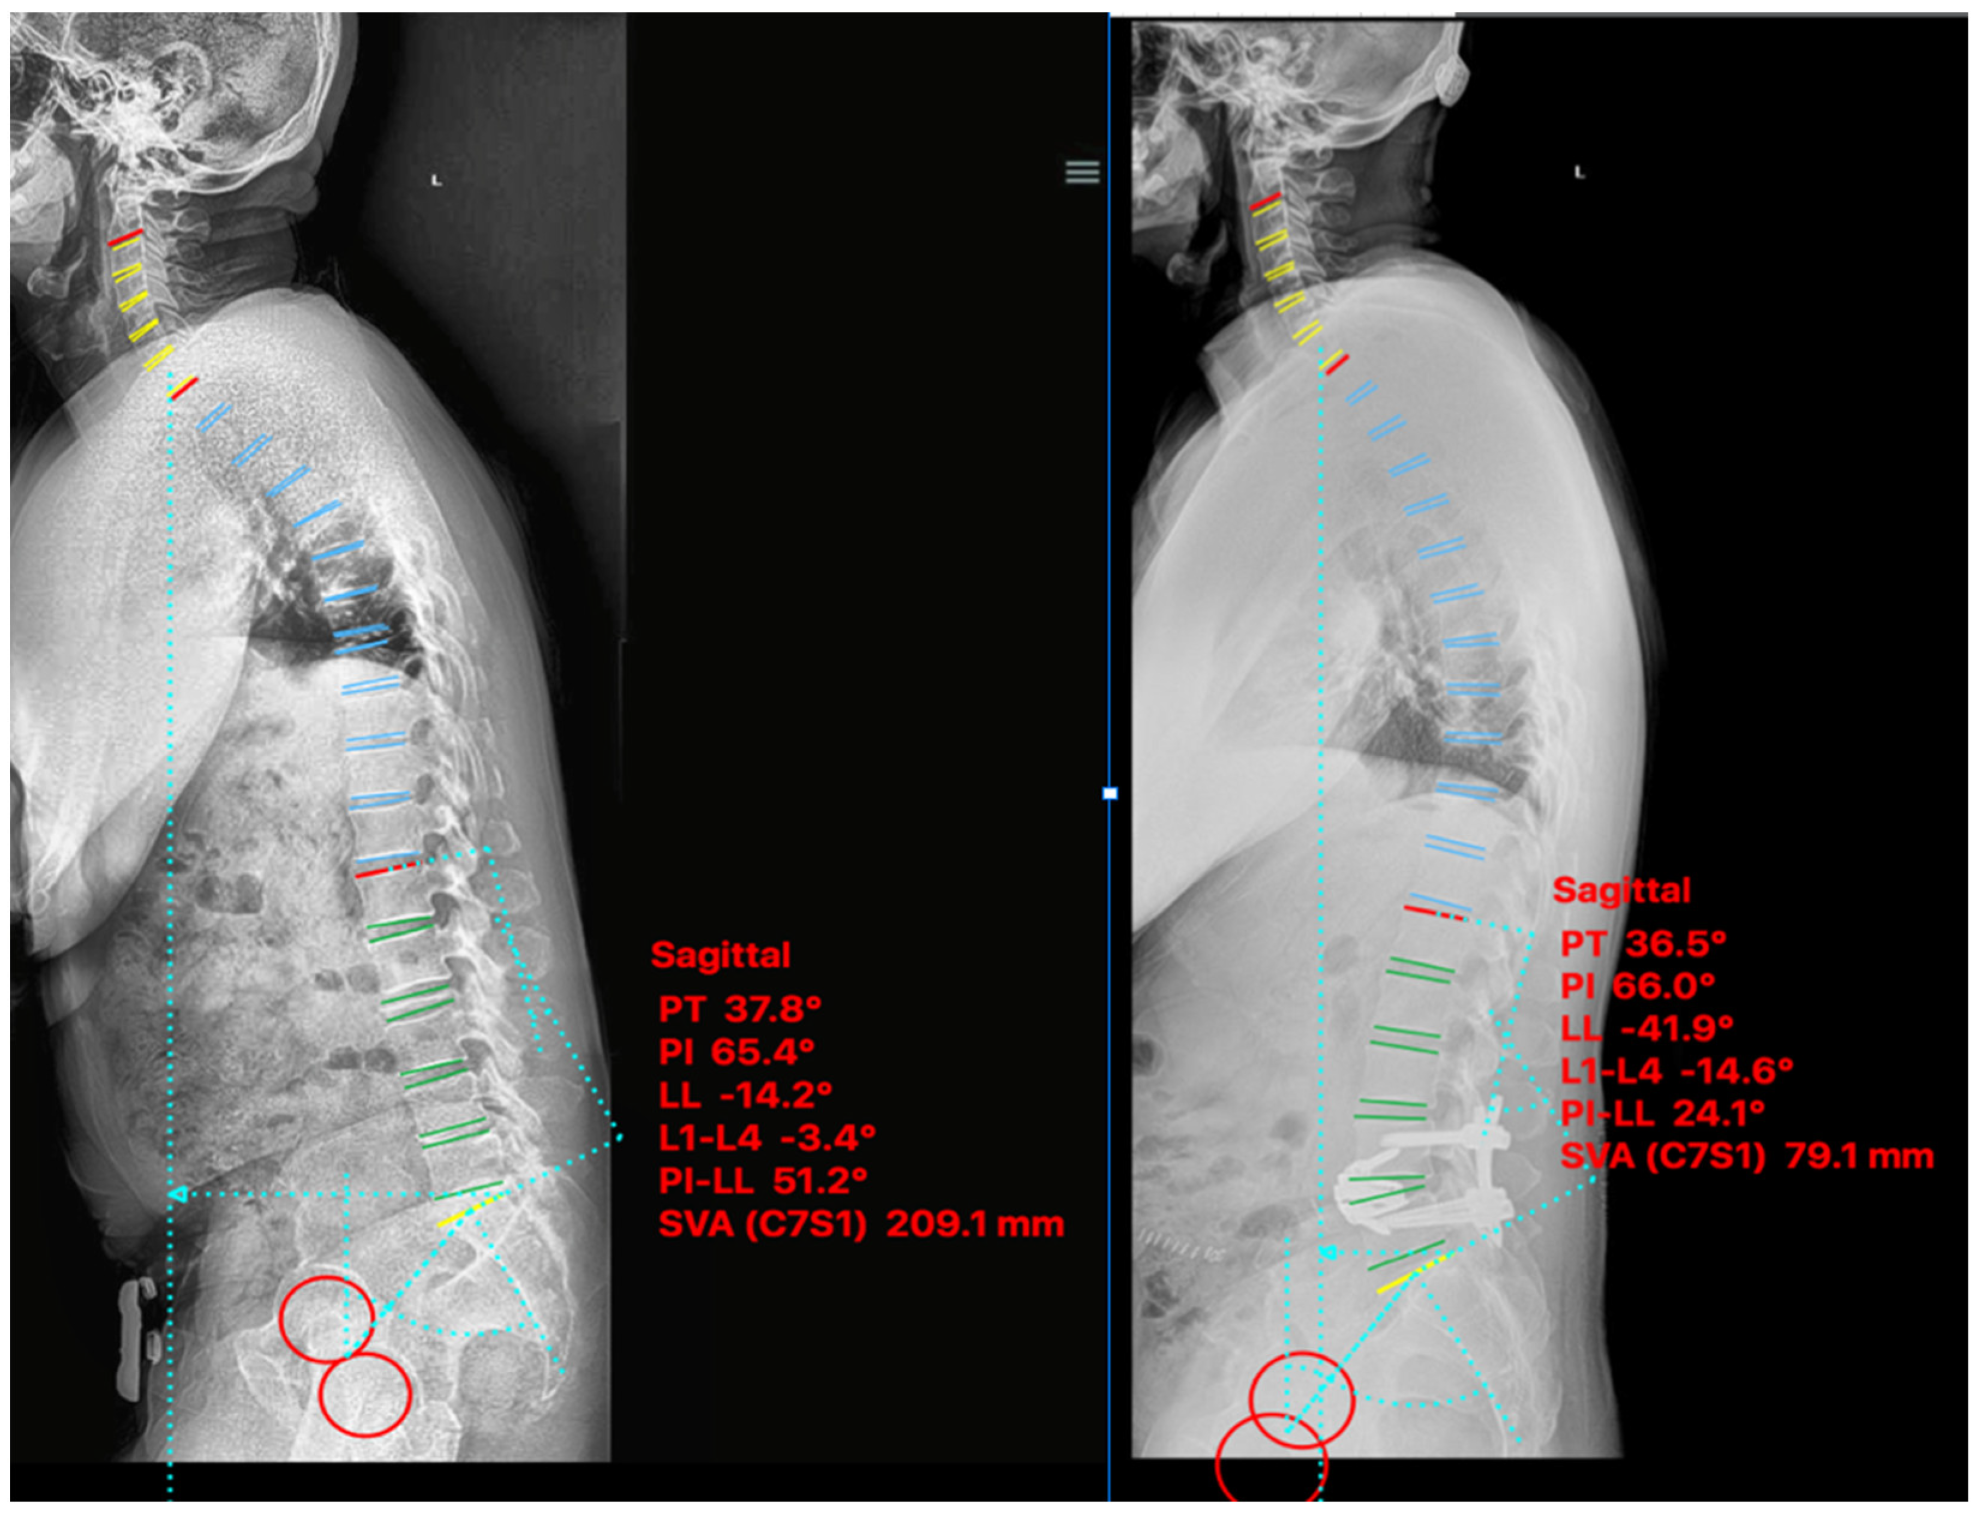

2.5. Non-ACR Cases

2.5.1. Case IV

2.5.2. Case V